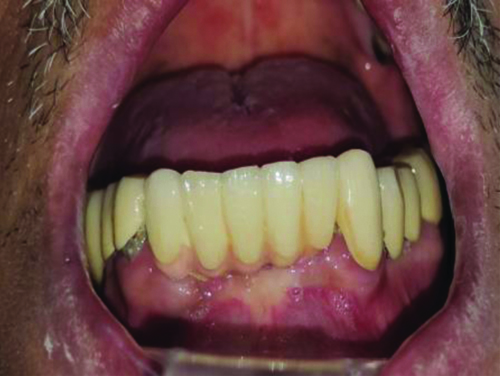

Once the former was retrieved [Table/Fig-4], an implant-level impression was recorded using putty and light body material and a new gingival former was placed [Table/Fig-5]. The final prosthesis was delivered to the patient in accordance with the principles of implant-protected occlusion [Table/Fig-6].

New gingival former placed after making impression.